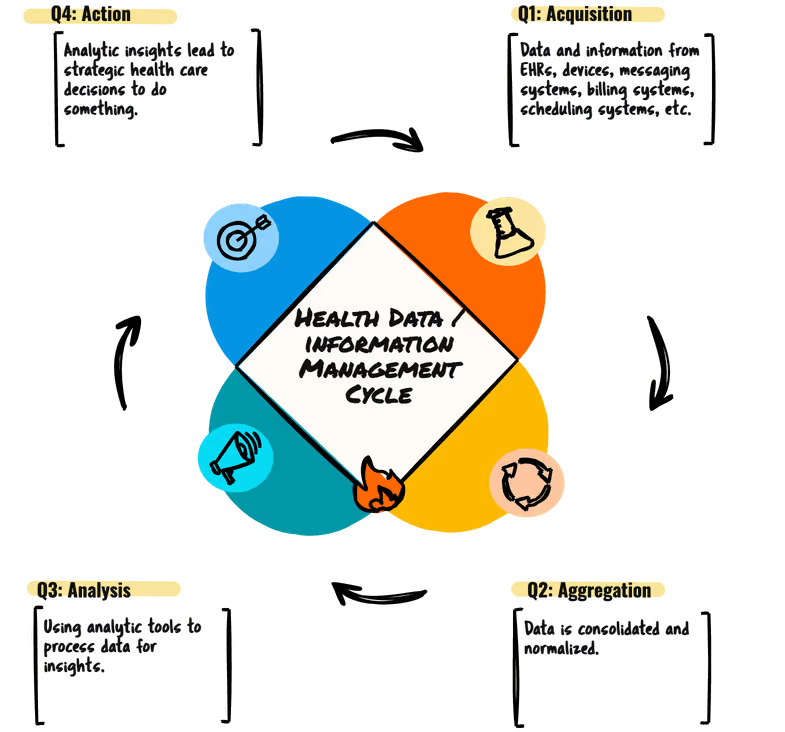

By JACOB REIDER I haven’t blogged this yet, which kinda surprises me, since I find myself describing it often. Let’s start with an overview. We can ….